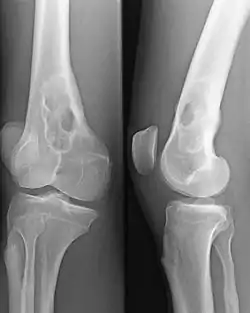

Un plasmocytome osseux solitaire du 1/3 inférieur du fémur dans le cadre d'un syndrome POEMS.